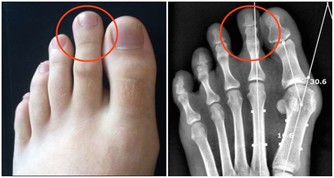

腎和頭部跟小指有關,所以如果你按壓小指,可以讓更為健康並舒緩頭痛。